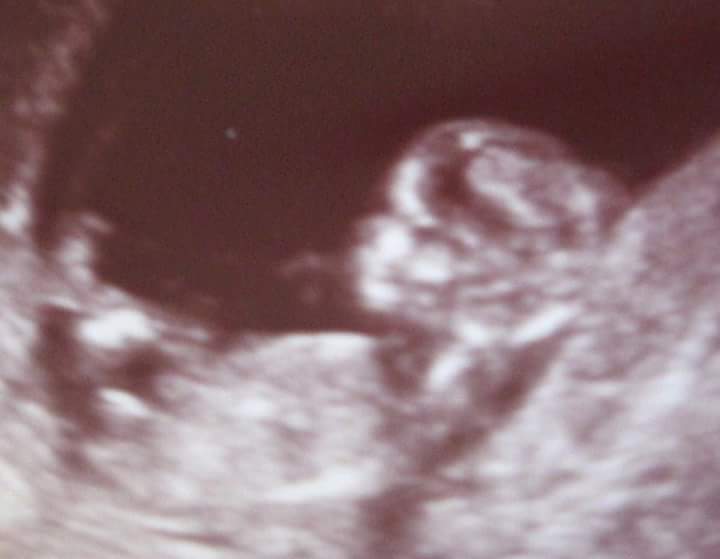

I'm 12 weeks today and had scan this AM. First PIC is of DS1 at 14 weeks second picture is of this bubs today at 12 weeks. Will be asking for a nub shot next week at 13 week scan but won't be having anatomy scan til mid March which feels ages away so for some fun please have a guess xxAttachment 29454Attachment 29455